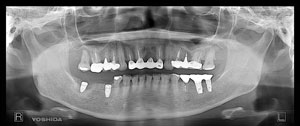

@@R.S‚³‚ñ@56Î —«  ‘åŠw‹³Žö @Žèp“ú@‚Q‚O‚O‚W”N ‚QŒŽ ‚X“úi“yj@㉺Š{  ƒm[ƒxƒ‹ƒKƒCƒhŽg—p@Ö¬“à’ÁÖ@•¹—p@@@

@@@@@ãŠ{  All on ‚U@‘¦Žž‰Ád@@

@@@@@@@@@@@@@ Rpl Tapered Rp  ‚P‚O mm(‚U–{)

@@@@@‰ºŠ{¶‰E@‘¦Žž‰Ád@ ‚R Unit Bridge@

@@@@@@@@@@@ @Rpl Tapered Rp  ‚P‚O mm(‚S–{)@@–ƒWƒ‹ƒRƒjƒAƒNƒ‰ƒEƒ“‚ÅÅI•â’Ô